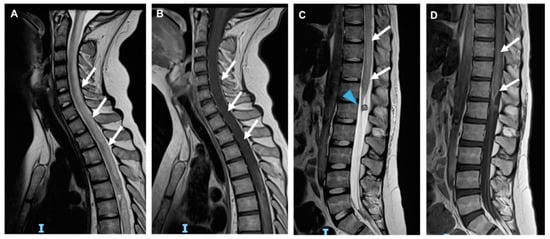

3.6. Radiation-Induced Cerebrovascular Disease

- Roongpiboonsopit, D.; Kuijf, H.J.; Charidimou, A.; Xiong, L.; Vashkevich, A.; Martinez-Ramirez, S.; Shih, H.A.; Gill, C.M.; Viswanathan, A.; Dietrich, J. Evolution of cerebral microbleeds after cranial irradiation in medulloblastoma patients. Neurology 2017, 88, 789–796. [Google Scholar] [CrossRef] [Green Version]

- Murphy, E.S.; Xie, H.; Merchant, T.E.; Yu, J.S.; Chao, S.T.; Suh, J.H. Review of cranial radiotherapy-induced vasculopathy. J. Neuro-Oncol. 2015, 122, 421–429. [Google Scholar] [CrossRef]

- Bavle, A.; Srinivasan, A.; Choudhry, F.; Anderson, M.; Confer, M.; Simpson, H.; Gavula, T.; Thompson, J.S.; Clifton, S.; Gross, N.L.; et al. Systematic review of the incidence and risk factors for cerebral vasculopathy and stroke after cranial proton and photon radiation for childhood brain tumors. Neuro-Oncol. Pract. 2021, 8, 31–39. [Google Scholar] [CrossRef]